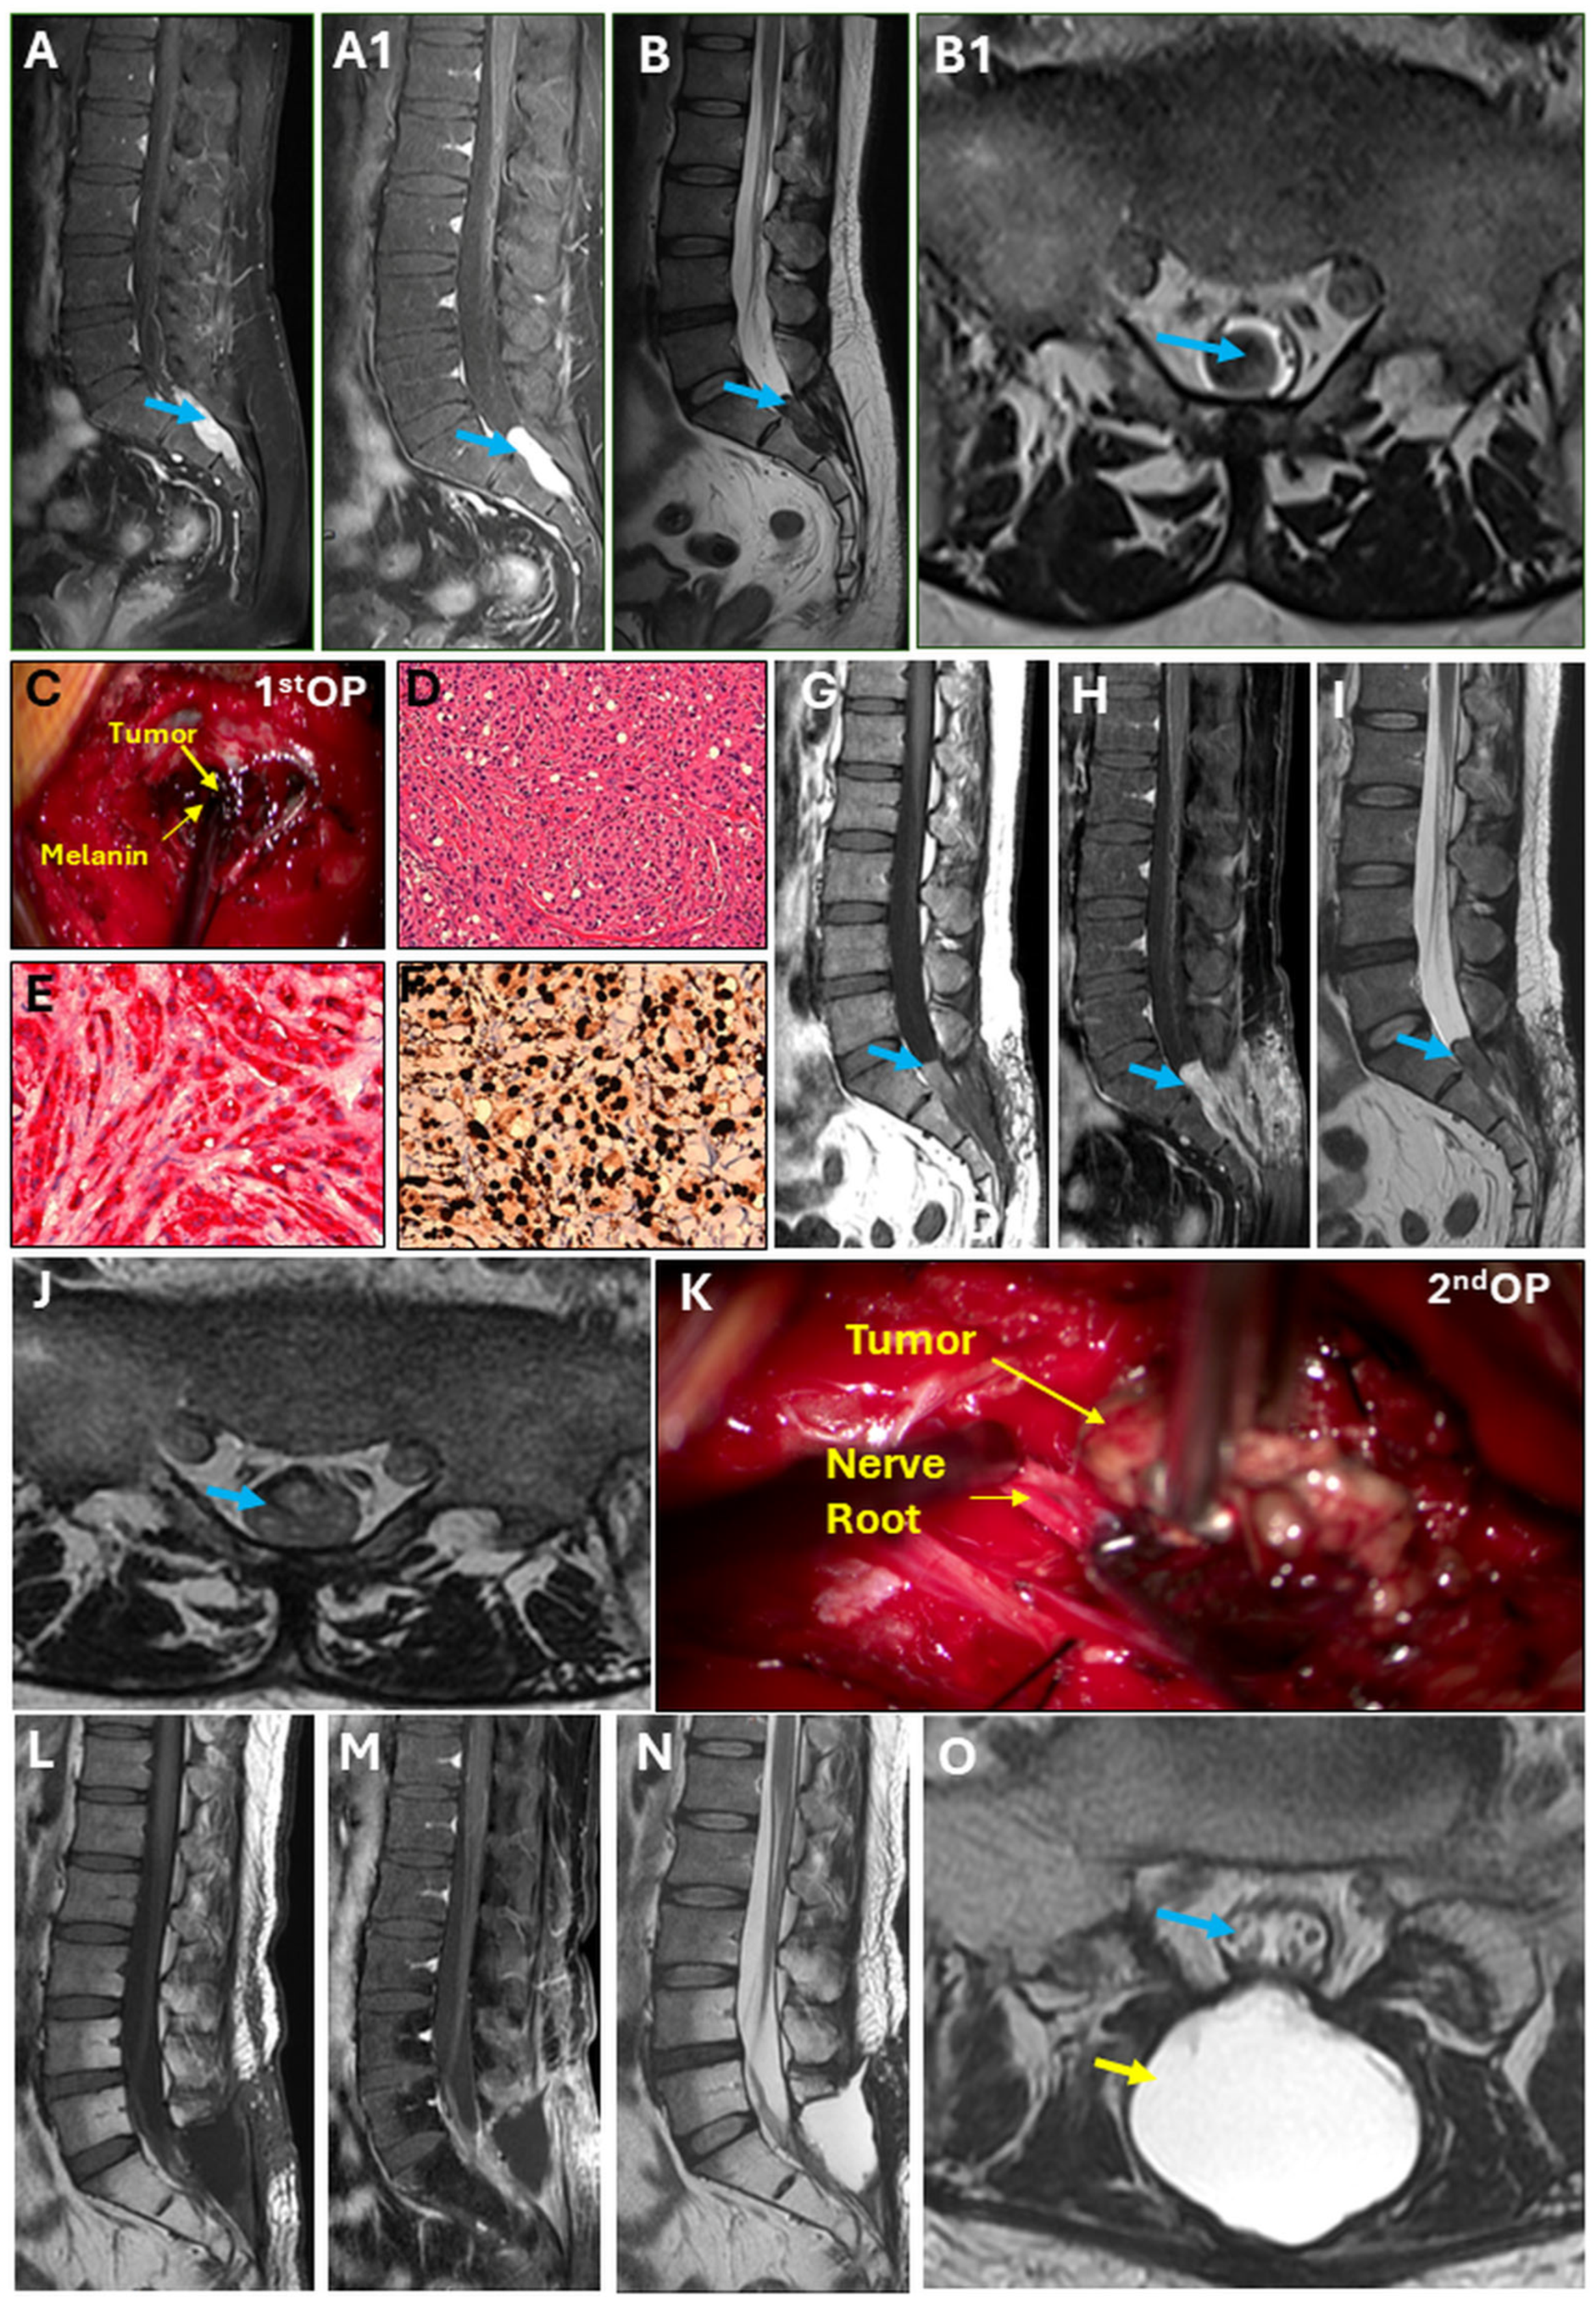

Intradural Melanotic Schwannoma of the Sacral Spine: An Illustrated Case Report of Diagnostic Conundrum

2. Detailed Case Presentation

Surgical Technique